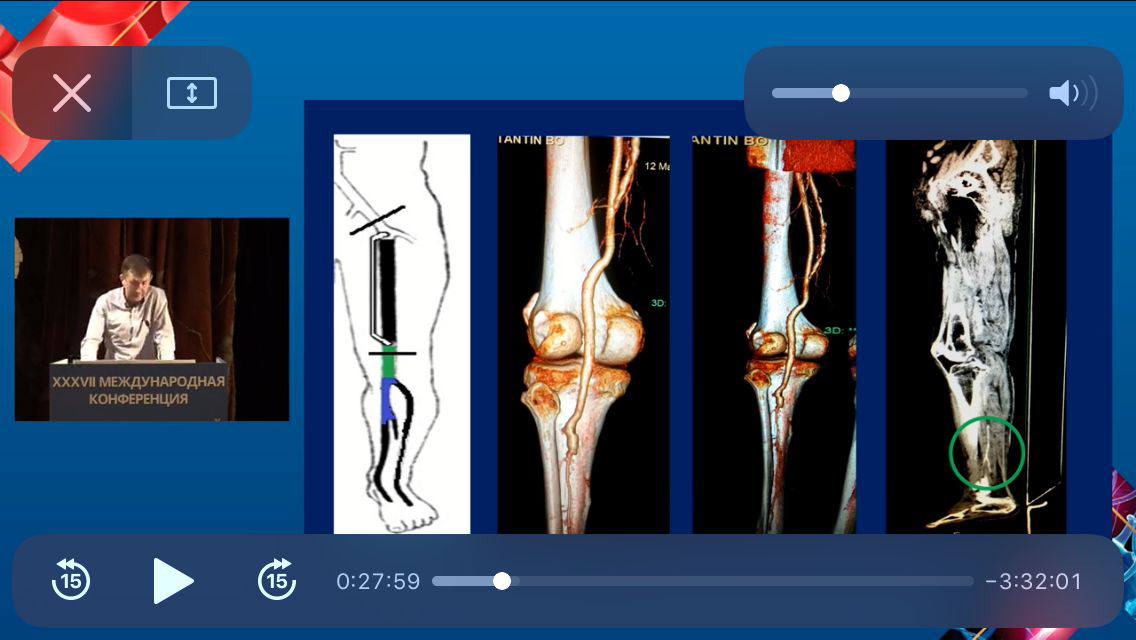

Ведущие врачи - сосудистые хирурги нашей клиники - Ильдар Галиевич Халилов и Наиль Ринатович Закиржанов - представили опыт своей работы - результаты каротидной эндартэрэктомии, выполненной в острейшем периоде ишемического инсульта. Работа вызвала активное обсуждение у собравшихся.